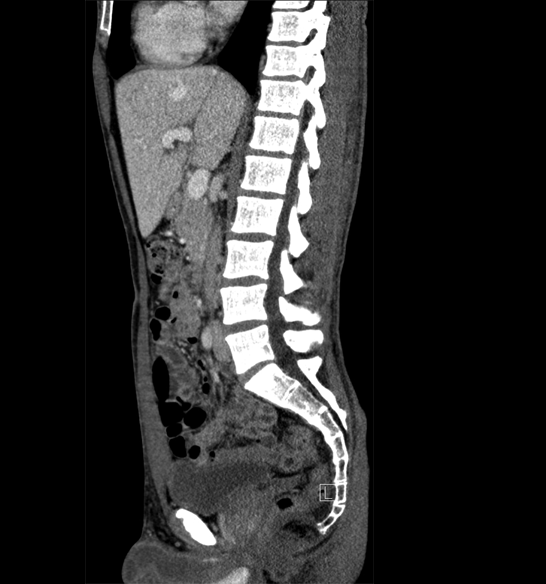

Body

Covers abdominal CT anatomy.